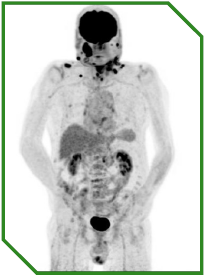

Paciente masculino de 74 anos com carcinoma espinocelular de cabeça e pescoço recorrente/metastático (R/M HNSCC) de orofaringe em base de língua, p16 positivo, previamente tratado com cirurgia extensa e radioquimioterapia adjuvante. Apresentava recidiva metastática predominantemente cutânea, alta expressão de PD‑L1 (CPS 60), ECOG‑PS 2 e limitações clínicas e geriátricas que restringiam a utilização de quimioterapia sistêmica. Diante desse contexto, foi selecionada imunoterapia isolada como estratégia de primeira linha no cenário metastático.